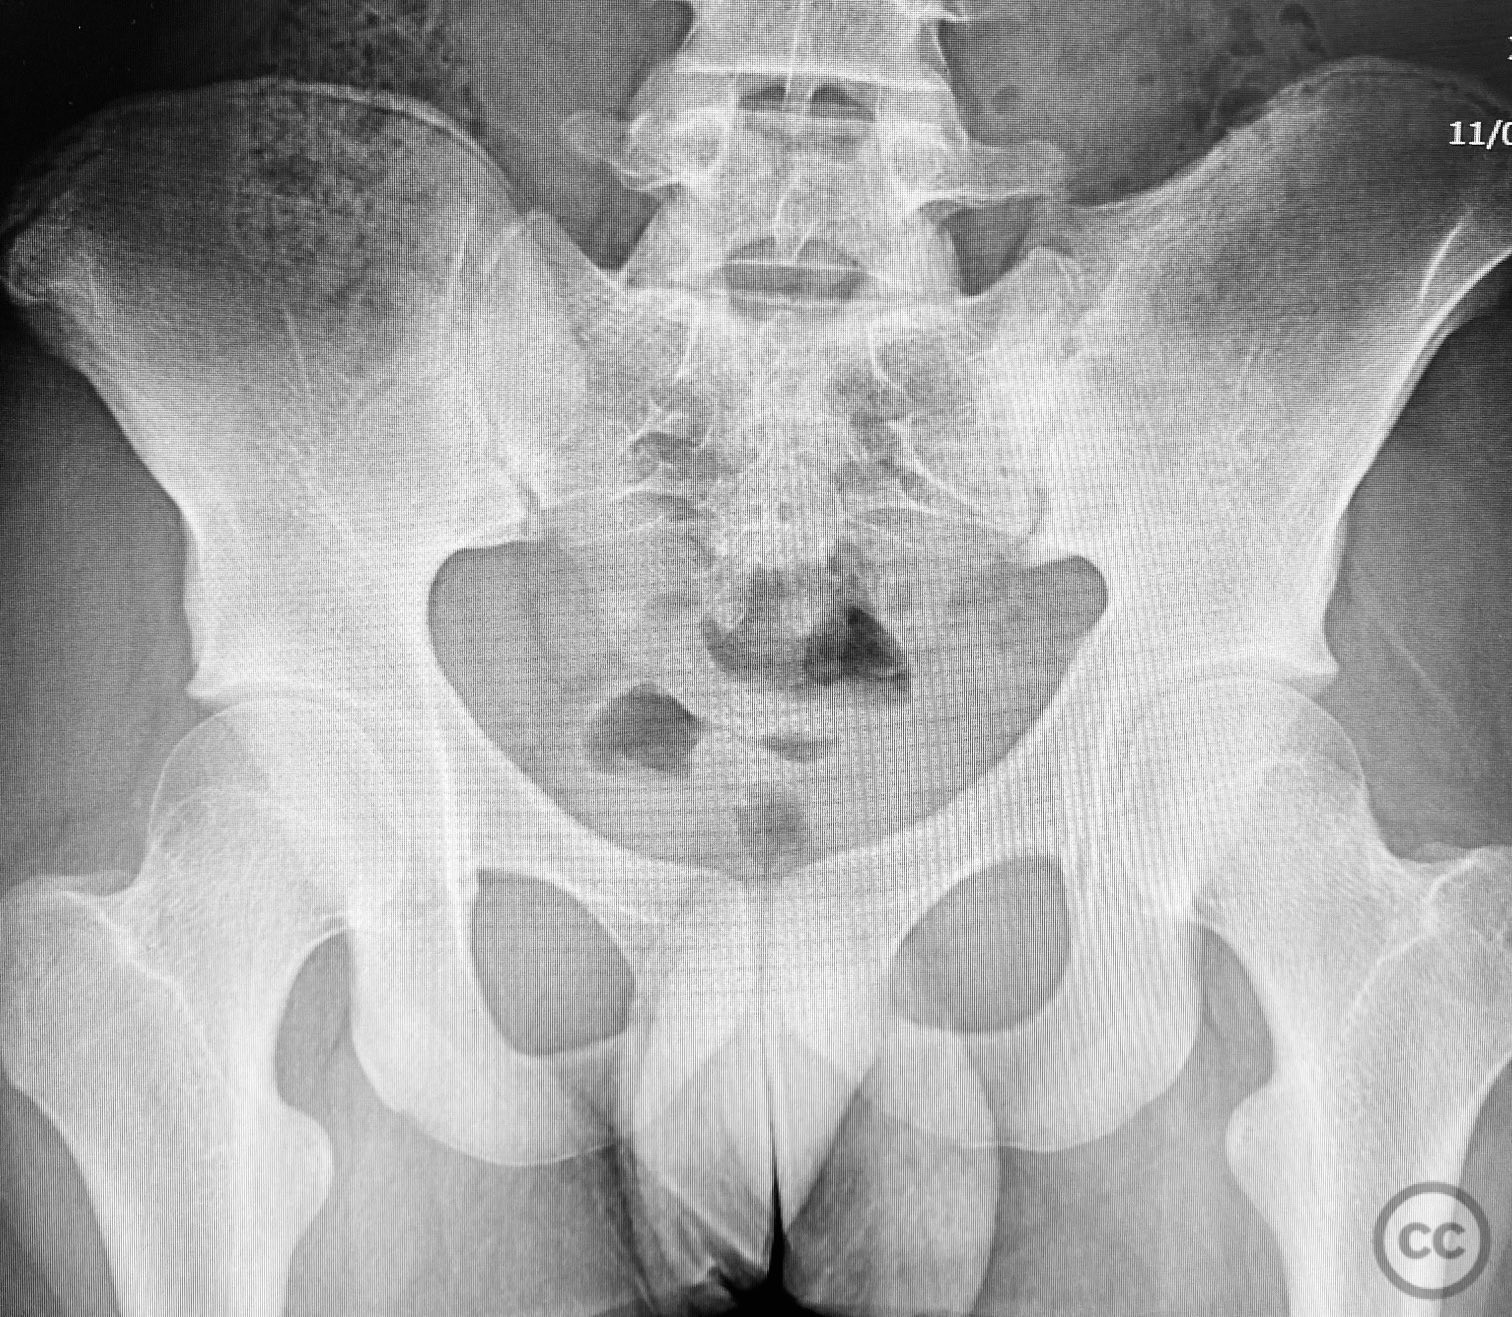

Clinical and radiological findings:  A 7-year-old male sustained a crush injury resulting in an unstable pelvic ring injury. Initial clinical assessment revealed no neurovascular compromise. Radiographs demonstrated a displaced fracture involving the superior pubic ramus and a posterior pelvic ring injury, consistent with an AO/OTA 61-C1 classification. No open wounds or associated visceral injuries were reported.